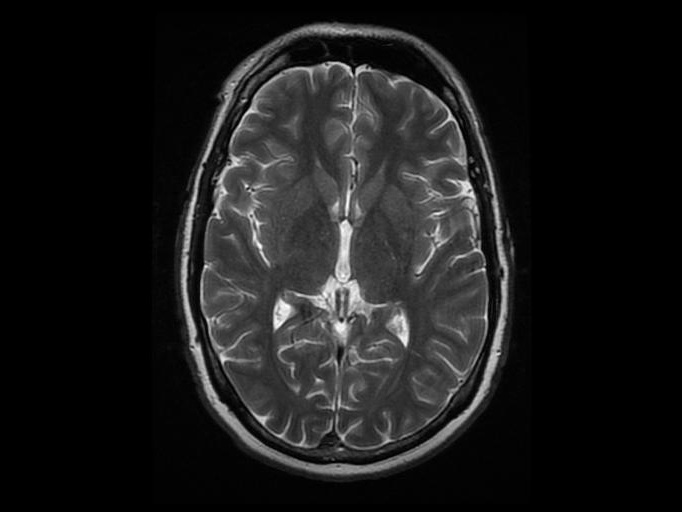

In a new study, MRI scans revealed that women's brains get re-wired during pregnancy. Jeffrey Hatcher via Flickr CC By 2.0

To pinpoint the exact mechanism involved, Xu and the rest of the team gave the 21 human participants a test, called a stop signal task, while they were in a fMRI machine. “It involved a cancellation of a movement that has already been made,” Xu says. In this case, the movement was eye movement: the participants were shown a signal, either to the left or the right, and they had to move their eyes to look at the target as fast as possible. After they initiated the movement, they were shown either a blue or yellow circle—one which meant stop, and one that meant go—and had to either continue or cancel their eye movement.

The team took the additional step of tracking the effects of the same tasks on the brain of a monkey. Scientists are able to measure the response from individual cells of the monkey brain during a task, while in humans, they’re only able to see larger areas that come through on an MRI scan. “We have both monkey data and the human data on the task, so there’s converging evidence,” Xu says. “You’re looking at both the brain imaging and the direct neuronal response.”